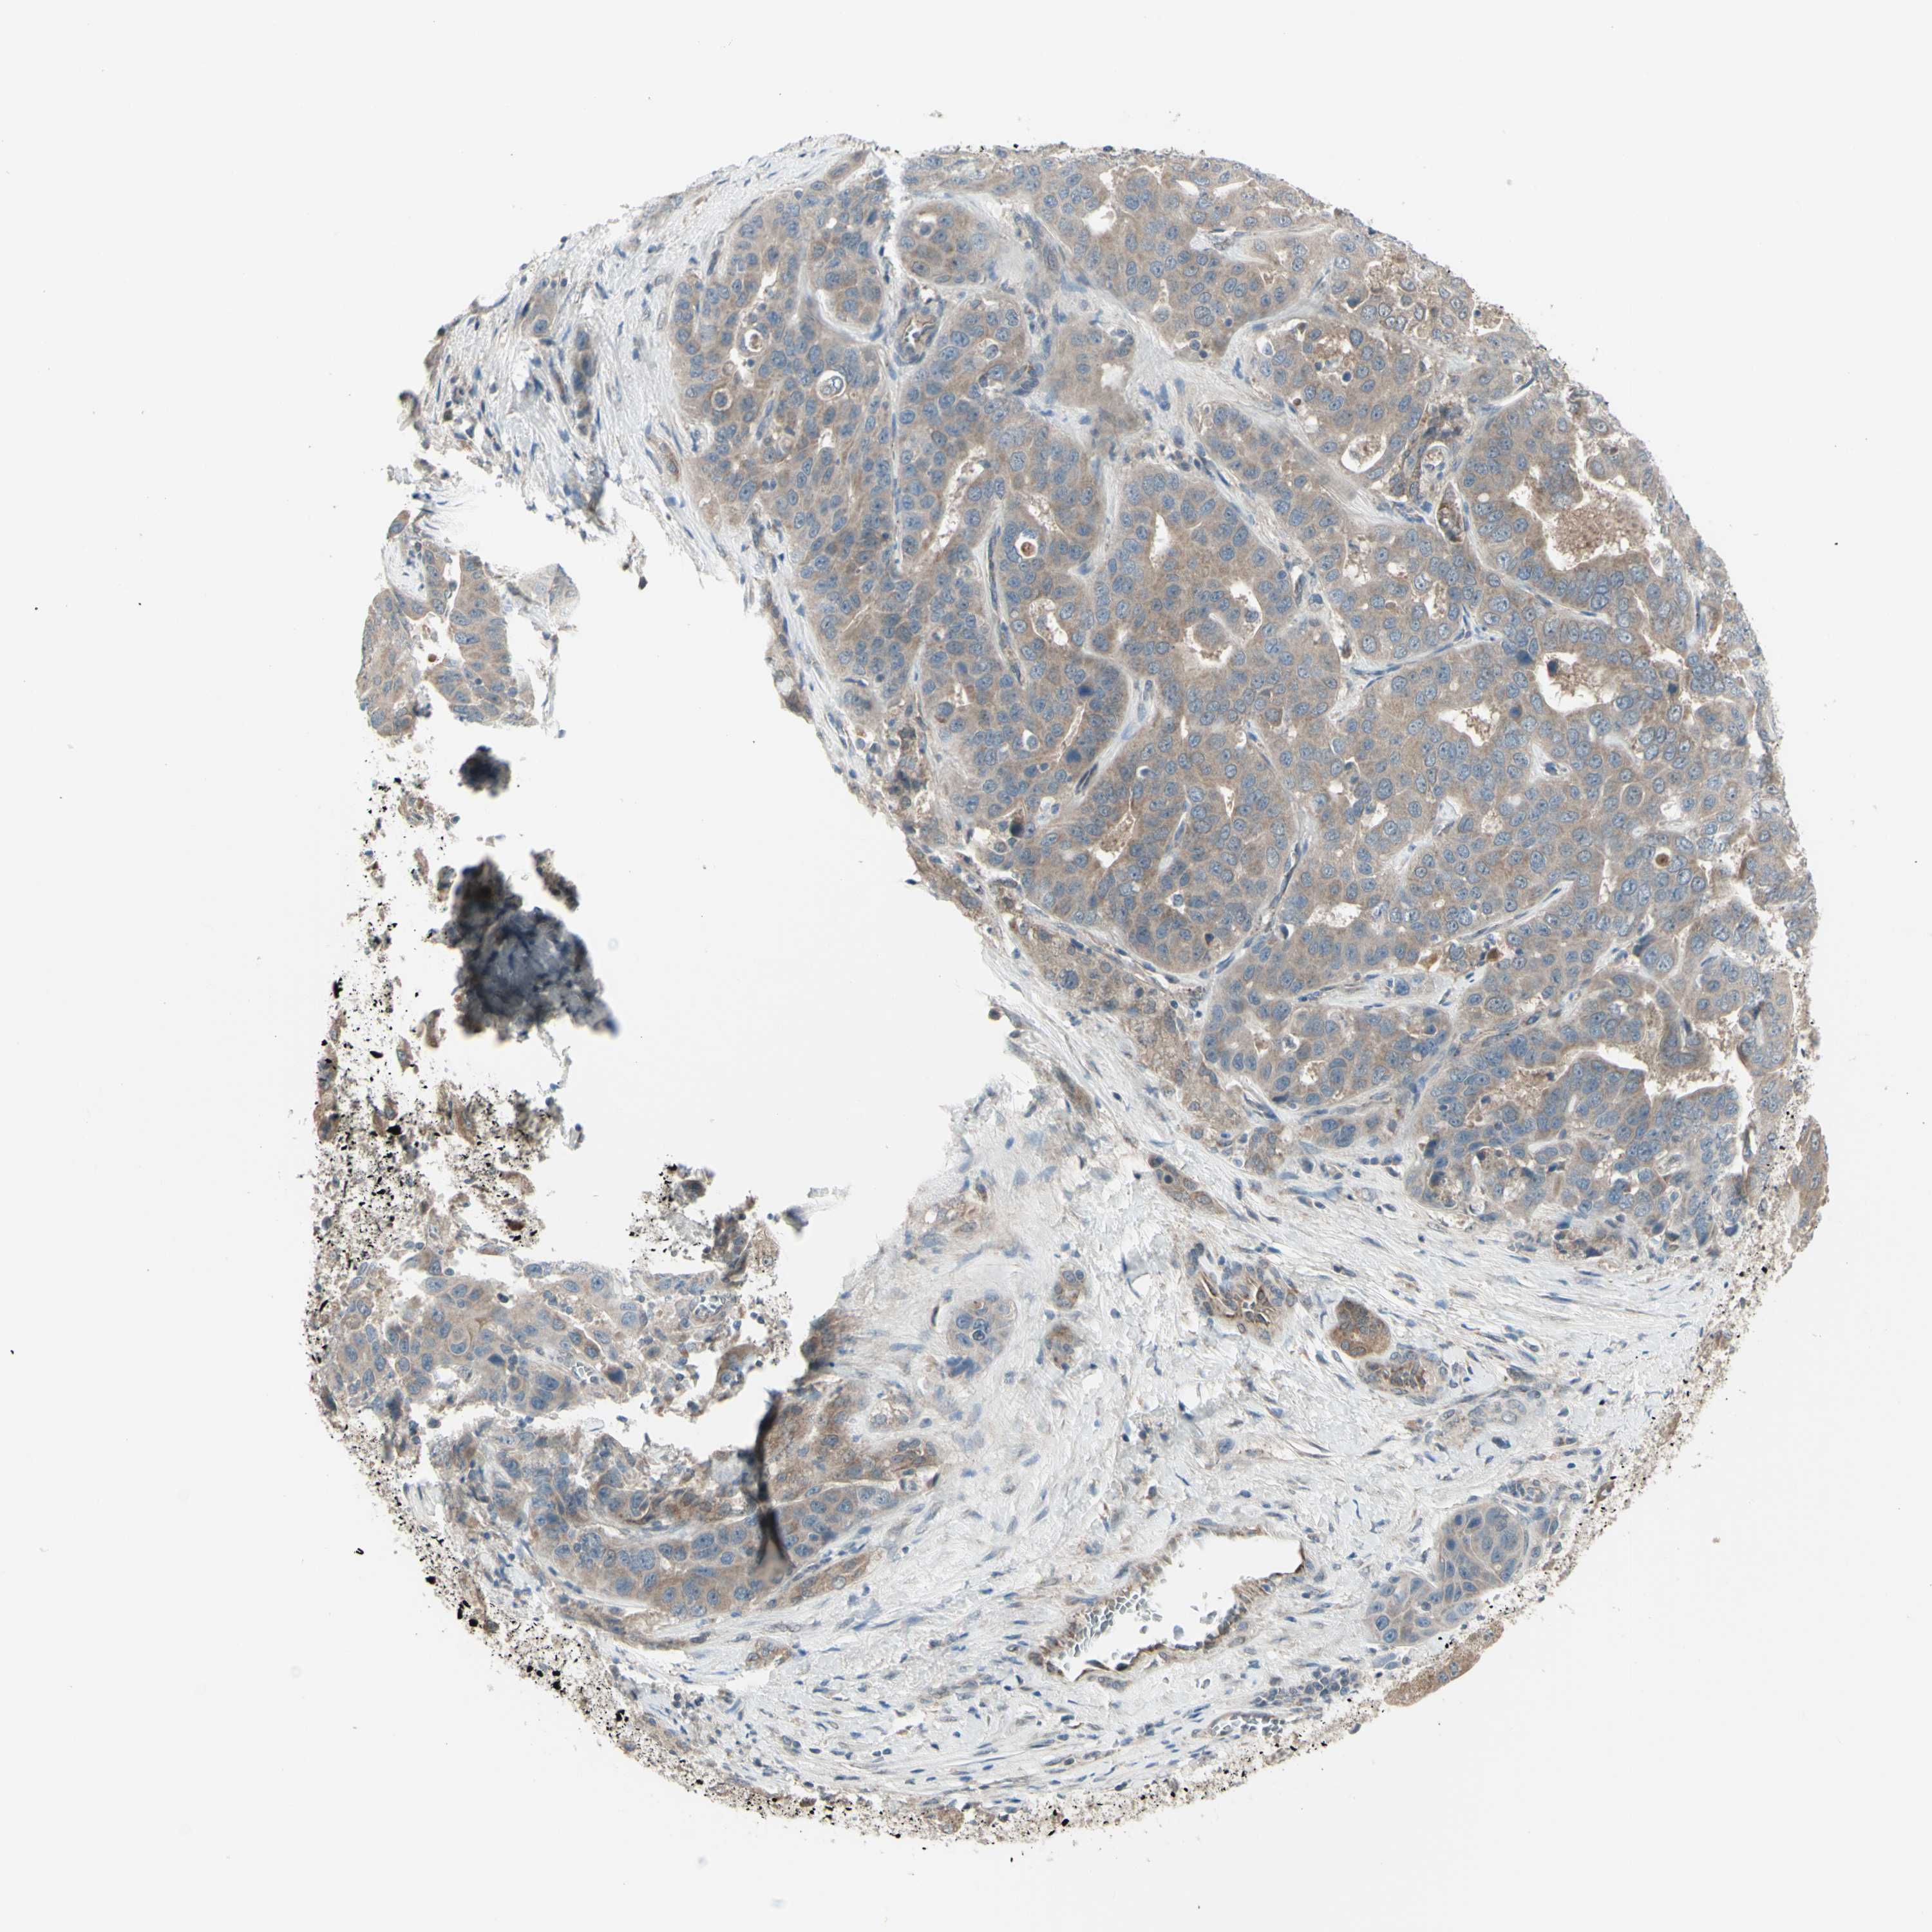

LIVER CANCER - Protein expressioni

A mouse-over function shows sample information and annotation data. Click on an image to view it in a full screen mode. Samples can be filtered based on level of antibody staining by selecting one or several of the following categories: high, medium, low and not detected. The assay and annotation is described here.

Note that samples used for immunohistochemistry by the Human Protein Atlas do not correspond to samples in the TCGA dataset.

Antibody stainingi

Antibody staining in the annotated cell types in the current human tissue is reported as not detected, low, medium, or high, based on conventional immunohistochemistry profiling in selected tissues. This score is based on the combination of the staining intensity and fraction of stained cells.

Each image is clickable and will lead to virtual microscopy that enables deeper exploration of all samples and also displays staining intensity scores, fraction scores and subcellular localization as well as patient and tissue information for each sample.

Antibody HPA010551

Staining

High

Medium

Low

Not detected

Intensity

Strong

Moderate

Weak

Negative

Quantity

>75%

75%-25%

<25%

None

Location

Nuclear

Cytoplasmic/membranous

Cytoplasmic/membranous,nuclear

Cholangiocarcinoma

Carcinoma, Hepatocellular, NOS